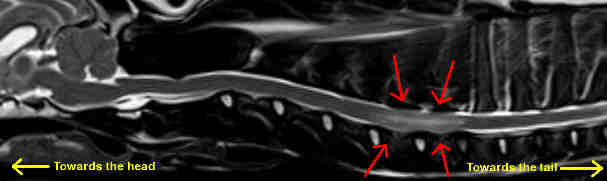

MRI with red arrows showing a fibrocartilaginous embolism in a dog's spinal cord.

(Photocredit: Bill Thomas Dipl.ACVIM (Neurology), University of Tennessee http://www.vet.utk.edu)

Magnetic Resonance Imaging (MRI) is not yet readily available to most veterinary practices but is likely to become the imaging modality of choice for the diagnosis of FCE. MRI is able to distinguish embolized areas of spinal cord from those with swelling or compression as long as at least 72 hours have elapsed from the initial event. Still, absolute confirmation of the FCE diagnosis requires a piece of spinal cord tissue for analysis and this is not something that would be done in a living patient. For the time being, diagnosis of FCE is made based on the clinical picture of a patient in the appropriate age group with an acute spinal deficit, no other abnormalities on imaging and no painful areas.